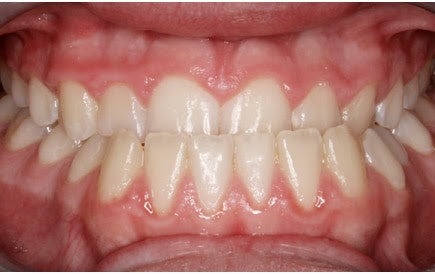

انواع کراس بایت (کراس بایت یک طرفه)

کراس بایت یک طرفه